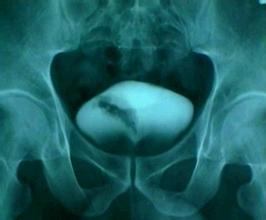

膀胱癌的晚期症状四:血尿

血尿是膀胱癌的晚期症状,特别是间歇性无痛肉眼血尿为膀胱肿瘤常见的病状,80%病人就诊时有血尿,17%血尿严重。由于血尿 常间歇出现、加重,容易给病人以“治愈”的错觉,以致延误了时间。